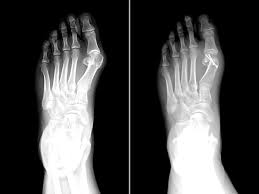

Ayak Bilek Ameliyati Fiyatlari Arsivleri Doc Dr Melih Malkoc